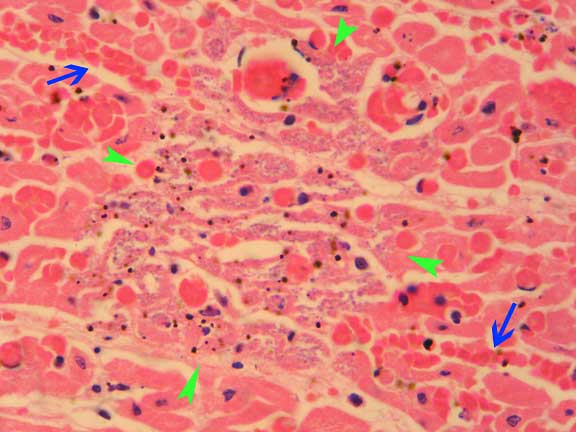

Haematoxylin & Eosin (x1000)

There are extensive areas of haemorrhage throughout the myocardium (arrows) with occassional foci of necrosis of myofibres and associated minieralisation of the necrotic fibres (area bounded by arrowheads).

There is also a staining artefact in this slide - what are the small dark granules seen diffusely thorughout the section?